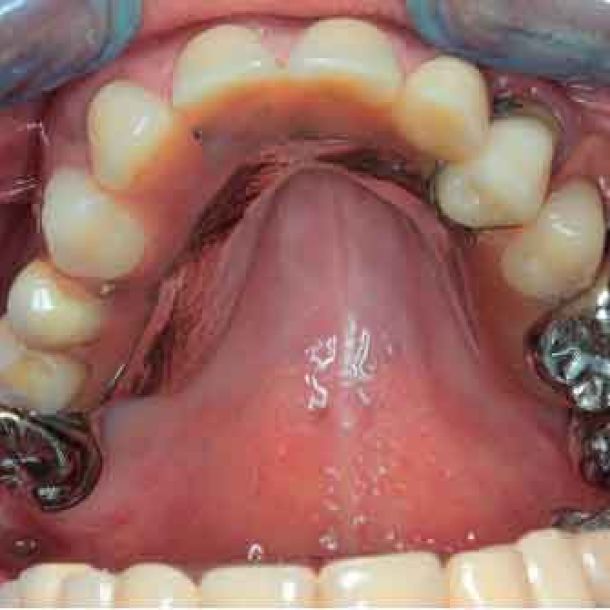

étape 4 - EXPORT DES DONNées vers le laboratoire

Lors du premier rendez-vous, la collecte de données complète est essentielle. Des photos aux fichiers DICOM segmentés et aux données de mouvement de la mâchoire, toutes les informations sont intégrées dans le logiciel TWIM, simplifiant la communication avec le laboratoire dentaire.

- Photos

- Scans IOS (incorrects mais toujours utiles pour le technicien dentaire)

- Fichiers DICOM, segmentés en fichiers STL

- Données de mouvement de la mâchoire : données individuelles du patient pour paramétrer l'articulateur virtuel

- Facescan (optionnel)

L'ensemble des données est envoyé au laboratoire pour concevoir les provisoires.